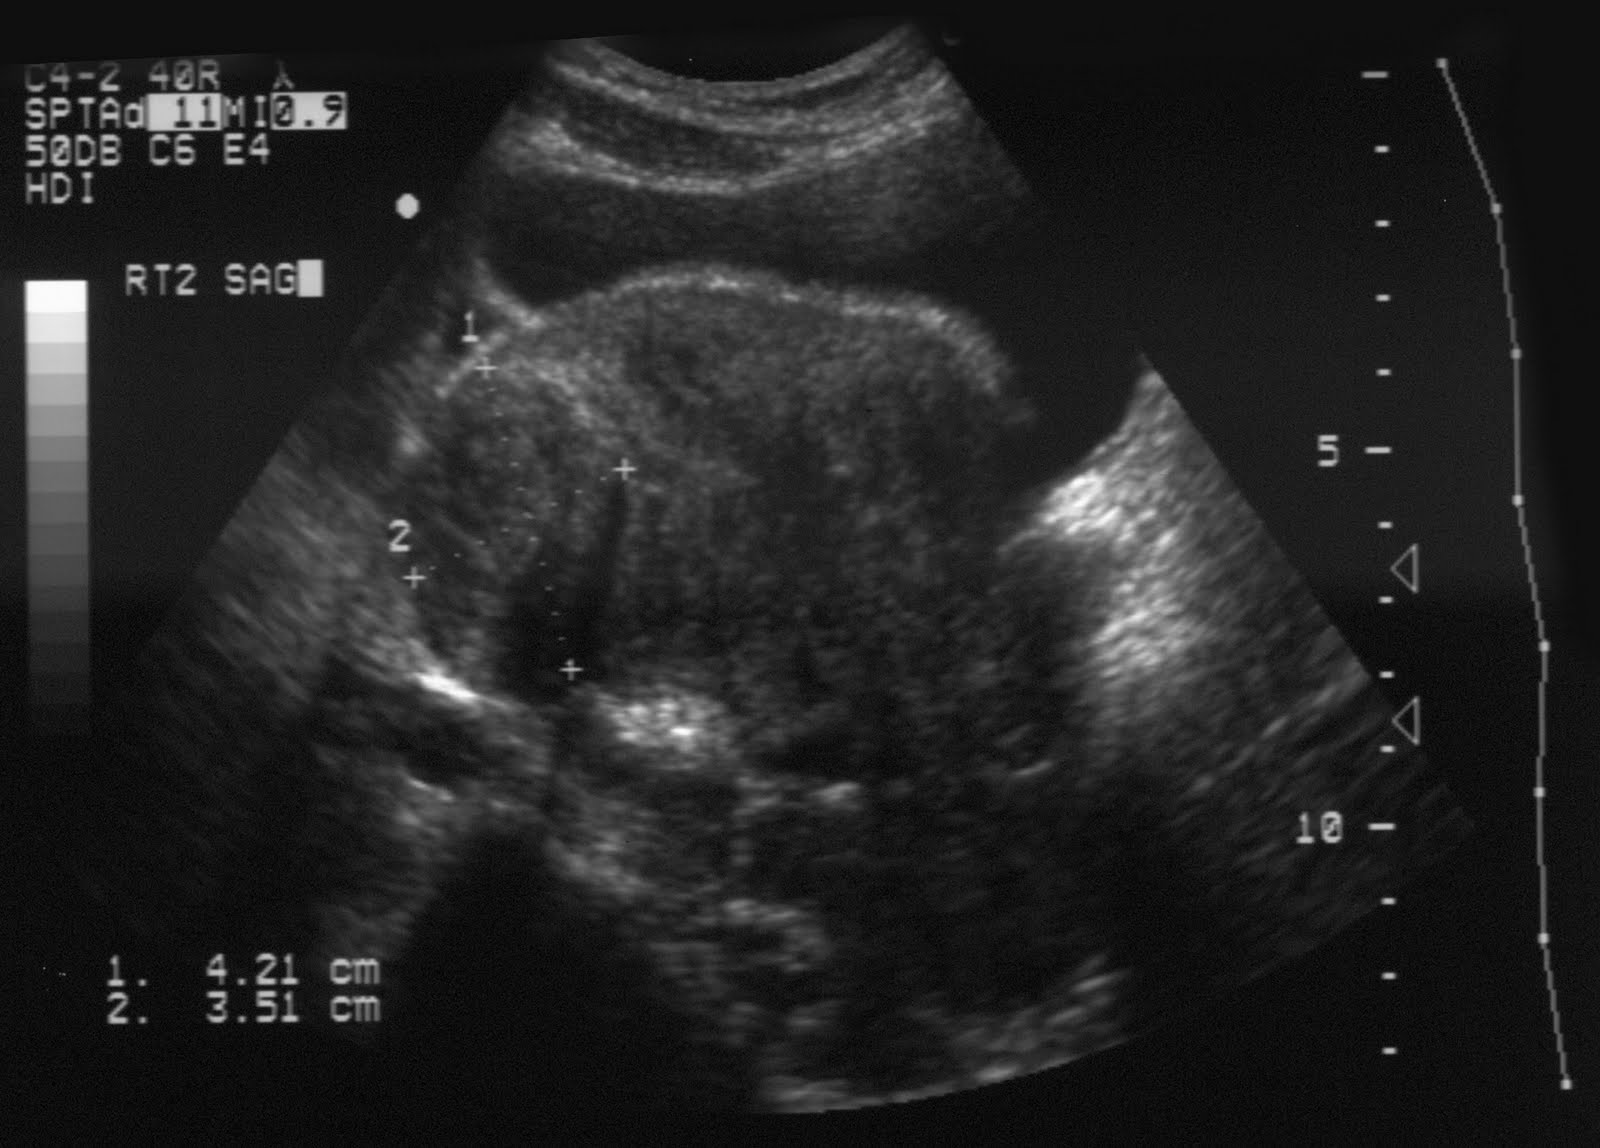

Gambar Usg Tumor Rahim

Tumor Kandungan Mioma Kista | pengobatan penyakit tumor | gangguan kesuburan Obat Herbal Kanker Rahim dan Serviks Hamil anggur - gejala, penyebab, dan cara menanganinya | theAsianparent Indonesia KESEHATAN PASIEN: January 2013 Dr.prima - dokter spesialis kandungan - “Tumor Mioma saat hamil” Tumor pada otot dinding rahim dikenal juga sebagai Mioma/fibroid. Asalnya dari otot rahim bentuknya benjolan daging mirip bakso. Beda dengan kista, benjolannya BILIK SONOGRAFER : Kista Ovarium Cara Membaca Foto USG: 8 Langkah (dengan Gambar) - wikiHow MACAM-MACAM KISTA. Dari USG bisa… - dr Yudhistya SpOG | Facebook Pertama di Dunia, Dokter Berhasil Angkat Tumor Janin dalam Rahim Gisantia Bestari — Hamil Dengan Rahim Spesial Alasan Perempuan Perlu USG Sekali Setahun KB Spiral Wanita Ini Menembus Dinding Rahim Hingga Kandung Kemih, Jarang Terjadi Tapi Risikonya Fatal! - Semua Halaman - Grid Health 5 Langkah Membaca Hasil USG yang Bisa Bunda Pelajari Kista di Rahim | Sehat PLUS Cantik Kista 5 Kg Ibu Hamil Hilang Tanpa Operasi Halaman all - Kompasiana.com Terjadi Lagi, Bayi Baru Lahir Ini ‘Mengandung’ Janin Kembarannya Sendiri Sejak dalam Kandungan - Semua Halaman - Grid Health Kanker Payudara: Setelah Kemoterapi dan Radioterapi Kanker Menyebar ke Hati Nya – Mengenal Kanker Dokter Chandra: Rahim Membesar Belum Tentu Hamil, Bisa Jadi Tumor - Padang Media Apa Sebab Rahim dan Indung Telur Tak Berkembang? | Kaltim Post Ingin Terhindar dari Kista? Jauhi 4 Jenis Makanan Enak Ini Sekarang! - Semua Halaman - Grid Health MACAM-MACAM KISTA. Dari USG bisa… - dr Yudhistya SpOG | Facebook Tadinya Diperkirakan Tumor Rahim yang Lengket Usus, Taunya ‘GIST’ - Kompasiana.com Tumor Kandungan (Miom, Kista) – ask-dr. David Mayndra Utama, SpOG Mengenal Kehamilan Kosong atau Blighted Ovum (BO) - Bidanku.com Harus Operasi Rahim Karena Infeksi Suntik KB, Kisah Wanita Ini Pilu - Lifestyle Fimela.com Kesha Ratuliu Ungkap Hasil USG Payudara, Jangan Tertukar, Ini Beda Tumor dan Kista - Halaman all - TribunStyle.com wanita wajib tahu, inilah rahim sehat - YouTube Bagaimana Cara Membaca Hasil USG? • Hello Sehat Dokter Spesialis Kebidanan Dan Penyakit Kandungan T-end RI: Teknik Pemeriksaan USG Vesica Urinaria dan Uterus Tumor Kandungan Mioma Kista | pengobatan penyakit tumor | gangguan kesuburan Kenali Cara Membaca Hasil USG Untuk Tahu Kondisi Bayi - Ibupedia Bila Terpaksa Hanya Menyisakan Leher Rahim Si Nona Halaman all - Kompasiana.com Wanita Lajang Perlu Waspadai Penyakit Kanker Ovarium USG Payudara: Fungsi, Prosedur, dan Persiapan yang Diperlukan Hal-hal yang Dapat Menjadi Faktor Penyebab Posisi Janin Jadi Sungsang Penyebab janin dalam kandungan menghilang Selain Kehamilan, Tes USG Bisa Deteksi 5 Kondisi Ini MACAM-MACAM KISTA. Dari USG bisa… - dr Yudhistya SpOG | Facebook Ahli Kista: September 2013 5 Tanda Kamu Mungkin Terkena Kanker Rahim - Alodokter Mengenal Istilah pada Hasil USG Kehamilan di Trimester Pertama Infertilitas atau susah punya anak – FeryWijayaSpOG operasiginekologi Instagram posts (photos and videos) - Picuki.com Kenali Perbedaan Tes USG Abdominal dan Transvaginal Tadinya Diperkirakan Tumor Rahim yang Lengket Usus, Taunya ‘GIST’ - Kompasiana.com Macam-macam USG untuk Pemeriksaan Kandungan | OTC Digest USG Transvaginal dan Perut, Mana yang Lebih Baik? Diagnosis Sindrom Ovarium Polikistik - Alomedika Tendangan Keras Bayi di Dalam Perut Bikin Rahim Sang Ibu Robek hingga Kaki Bayi Keluar - Halaman all - Tribun Medan Dikira Cuma Masuk Angin, Dokter Ini Tercengang Saat Temukan Kista Sebesar Bola Sepak di Dalam Perut Pasiennya! - Semua Halaman - Grid.ID Tumor jinak & mioma uteri Kesha Ratuliu temukan benjolan tumor di payudaranya, kenali gejalanya! | theAsianparent Indonesia Welcome to FITRULLAH DOT COM ******* Daily Note: Global Society Care and Research ! ****: Hasil Tes USG Penderita Tumor Payudara: Tumor Lenyap! Kehamilan Membuat Saya Terkena Kanker Serviks’ Operasi Pengangkatan MIOM Tanpa ANGKAT Rahim(dr Boy Abidin) - YouTube Kirain Turun Berok, Ternyata Hamil dan Akhirnya Keguguran (bagian 2) Hasil USG Tunjukkan Ada Gelembung dalam Rahim,Faktanya Bikin Wanita Menangis,Ternyata Janinnya - Tribun Sumsel Kumpulan Artikel Tumor Payudara Inilah Perbedaan antara USG 2D dan USG 3D Unggah Foto USG, Kesha Ratuliu Dikira Hamil Padahal Belum Nikah. Ternyata itu Bukan Foto Rahim Cara Membaca Foto USG: 8 Langkah (dengan Gambar) - wikiHow Pyometra, Penyakit Infeksi Rahim Pada Anjing - Kesehatan Anjing - AnjingKita.Com 5 Fakta Kista Coklat yang Harus Diketahui | Popmama.com Gejala Kanker Serviks, Penyebab, Biaya Berobat & Dokter - Smarter Health Miom - Gejala, penyebab dan mengobati - Alodokter Pemeriksaan USG Transvaginal vs USG Abdominal: Lebih Baik Mana? Muncul Tanpa Gejala, Ini 5 Cara Diagnosis Fibroid Rahim BAB II TINJAUAN PUSTAKA. Tumor ovarium adalah neoplasma yang berasal dari jaringan ovarium. Tumor ovarium - PDF Download Gratis Pengalaman ; Kista, Laparoskopi – Bayi Tabung – IVF | : : ZABANIYYAH : : Bagaimana Membedakan Tumor Jinak dan Ganas - Futuready Keguguran Bisa Dideteksi Dari Setiap Tahap Kehamilan – Apakabar Online Tumor jinak & mioma uteri 10 Ciri-Ciri dan Gejala Miom Rahim yang Mudah Dikenali | HonestDocs Kondisi Begini Membuat Wanita Harus Melakukan USG Transvaginal Manfaat USG Tidak Hanya Untuk Penentuan Jenis Kelamin Janin | Medicalogy MACAM-MACAM KISTA. Dari USG bisa… - dr Yudhistya SpOG | Facebook gambar pemeriksaan usg by aa craft USG Transvaginal, Pemeriksaan yang Ampuh Deteksi Penyakit di Area Panggul, Cek yuk! - Semua Halaman - Grid.ID Jual Manjur obat kanker leher rahim kista tumor kanker payudara rekomendasi - Kab. Cilacap - Toko Pengobatan Herbal. | Tokopedia Unggah Foto USG, Kesha Ratuliu Dikira Hamil Padahal Belum Nikah. Ternyata itu Bukan Foto Rahim Kista Fungsional, Bahaya Nggak Sih ? – esshintaku Tanda Janin Sedang Bermasalah dalam Rahim per-Trimester - Mommies Daily Diagnosis Penyakit Radang Panggul (PID) - Alomedika Genbest - Generasi Bersih dan Sehat 3 Cara Membaca Hasil USG yang Benar, Biar Nggak Salah Kaprah | merdeka.com Mioma Uteri | Gejala, Diagnosis, Pengobatan Apa saja kondisi rahim bermasalah yang perlu diwaspadai? Cara Membaca Foto USG: 8 Langkah (dengan Gambar) - wikiHow BAB II TINJAUAN PUSTAKA. Tumor ovarium adalah neoplasma yang berasal dari jaringan ovarium. Tumor ovarium - PDF Download Gratis Pakai USG, Janin Ini Menendang Keras Rahim Ibunya Hingga Kakinya Keluar, Dokter pun Panik - Tribun Pekanbaru Jual Produk Kista Rahim Herbal Murah dan Terlengkap Maret 2020 | Bukalapak Benjolan di Perut, Ini 7 Gejala Tumor Jinak Rahim 6 Potret Kondisi Suteng Pengasuh Arsy Hermansyah Pasca Operasi 10 Jam, Lemas Tak Berdaya - Kapanlagi.com Kenali Perbedaan Miom dan Kista - Investor.ID PEMERIKSAAN ULTRASONOGRAFI (USG) MUSKULOSKELETAL M BIOPRO ASLI Obat Herbal Miom Tanpa Operasi - Obat Ampuh Kista Ovarium - Kista Dermoid - Kanker Serviks - Kanker Rahim - Kanker Payudara - Tumor - Kanker Uterus Abnormal - BAB 2 TINJAUAN PUSTAKA Ciri-Ciri Rahim yang Sehat dan Subur, Wajib Diketahui Wanita USG, Ini yang Harus Anda Ketahui - Alodokter